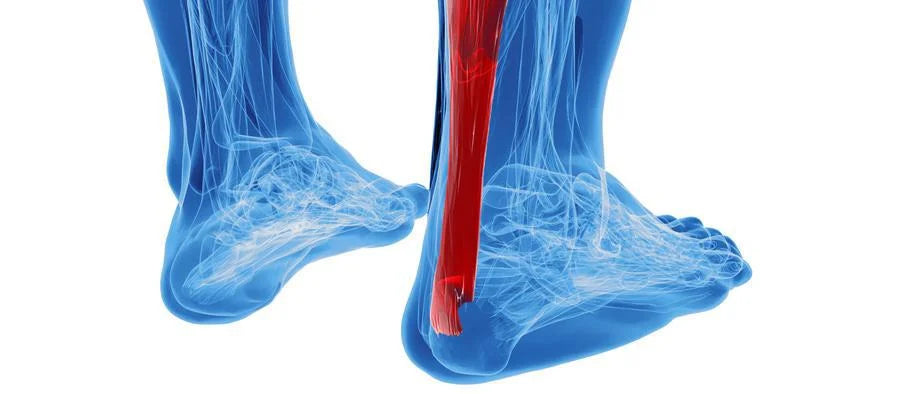

Tendons are tough bands of fibrous connective tissues that attach bones to muscles. Like ligaments (which connect bones to other bones), tendons are composed mainly of collagen.

- Achilles tendons which help move your foot up and down or side to side

- Achilles (heel)